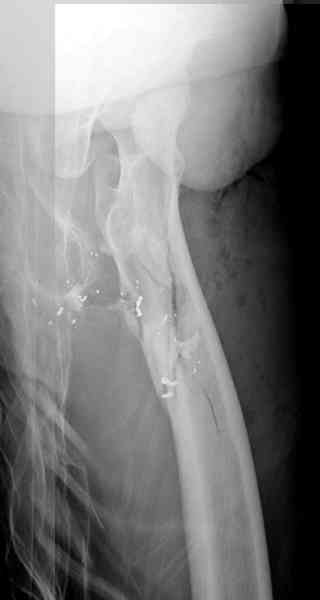

В нашем случае 21 летний боец уличного фронта, фиксацию провели на следующий день, зафиксирован интрамедуллярным штифтом. Не стали делать первичную хирургическую обработку точечной раны, зафиксирован как есть. Клинические снимки:

Вложение не в текстовом формате было извлечено…

Имя     : 4.jpg

Тип     : image/jpeg

Размер  : 28509 байтов

Описание: отсутствует

Url     : http://weborto.net:8080/pipermail/ortho/attachments/20081023/35009bb3/attachment-0012.jpg